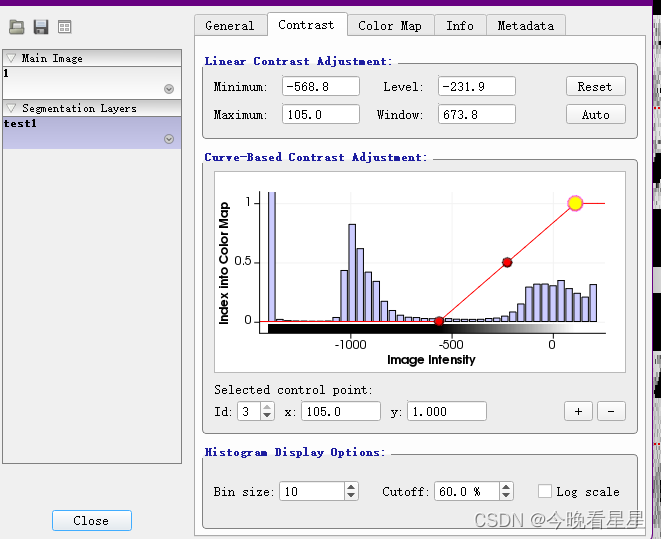

Contrast可用于调整窗宽窗位,主要是图像的对比度Color Map可用于调节显示的颜色,比如调节为伪彩,便于观察, 但常用的还是灰度图